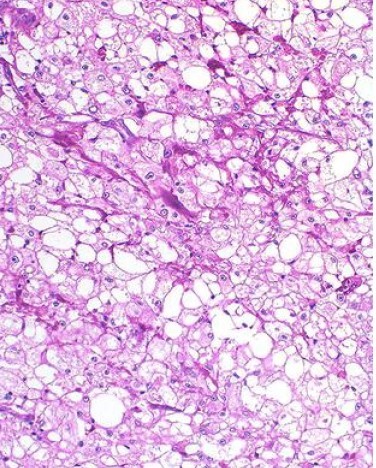

A 60-year-old man has a surgical excision of a brain mass; a photomicrograph of excised tissue is shown He has smoked 1 pack of cigarettes daily for the past 50 years. His blood pressure is 130/90 mm Hg.

Laboratory studies show polycythemia, hypercalcemia, and microscopic hematuria. Immunostaining of the tissue is positive for epithelial membrane antigen and negative for carcinoembryonic antigen. Which of the

following is the most likely site of the primary neoplasm?

Correct Answer: B.

Renal cell carcinoma (RCC) is an adenocarcinoma of tubular epithelial cells. RCC is the most common primary malignancy of the kidney and most commonly occurs in older male smokers. It can present with gross or microscopic hematuria, flank pain: weight

oss: or fever. Laboratory analysis may show polycythemia or hypercalcemia as a result of associated paraneoplastic syndrome production of erythropoietin or parathyroid hormone-related peptide. Hypercalcemia can also result from bony metastasis. Diagnosis of

RCC typically occurs with contrast-enhanced CT scan or MRI and is confirmed by biopsy at the time of nephrectomy. Biopsy of RCC is uniquely characterized by polygonal clear cells: because of the accumulation of lipid and carbohydrate content in the cells. It spreads hematogenously and commonly presents as a metastatic neoplasm. The brain and lung are frequent sites of metastasis.

Educational Objective: Renal cell carcinoma often presents in older men with a history of cigarette smoking, and the brain is a potential site of metastasis. Laboratory analysis may show hematuria along with hypercalcemia or polycythemia secondary to paraneoplastic syndromes. Histology typically demonstrates polygonal clear cells related to the accumulation of lipid and carbohydrate content in the cells.